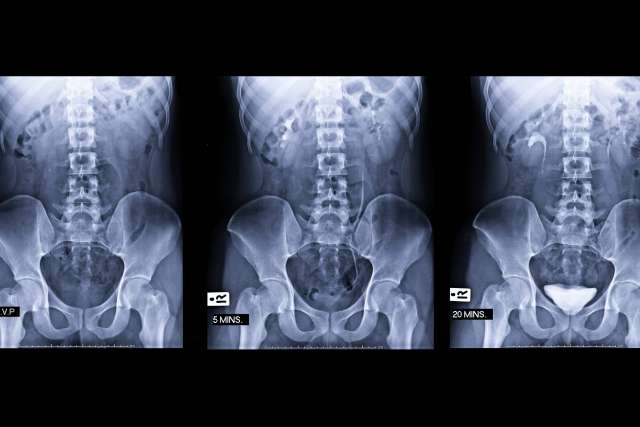

Prostate cancer scan